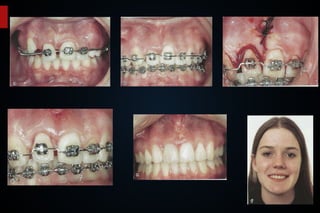

Periodontite Avançada, aparelho fixo durante 2 anos, resultados mantidos com uso de contenção.

7 anos após